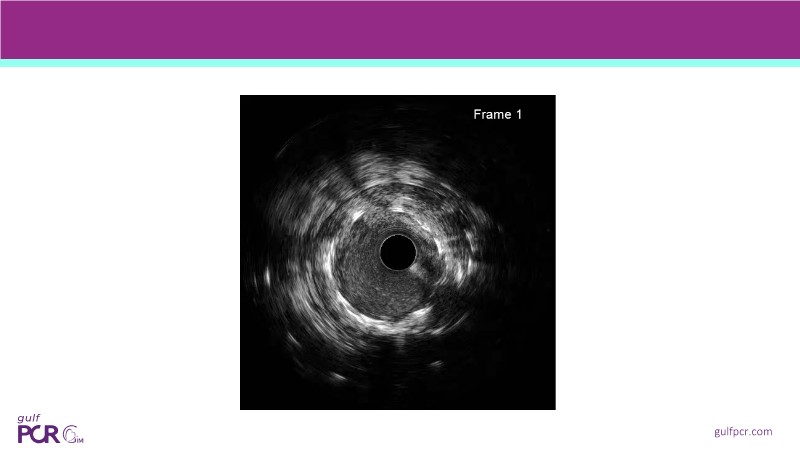

Calcified coronary lesions are a major challenge in PCI. This PCRGulf-GIM 2025 session showcases a complex case with intravascular imaging, highlighting how IVUS 123 guides each step.

From planning the procedure and understanding calcium distribution, to lesion preparation with modern modification tools, and post-PCI assessment to confirm stent expansion and detect complications, this session demonstrates practical, imaging-driven strategies.